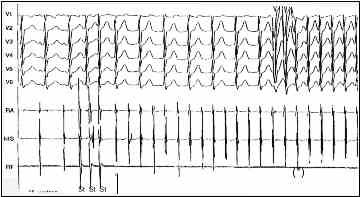

Figura 7: Inducción de una TRI (flecha) mediante tres extraestímulos. Los primeros complejos QRS de la taquicardia son conducidos con un bloqueo A:V 2:1. Posteriormente desaparece dicho bloqueo (*)